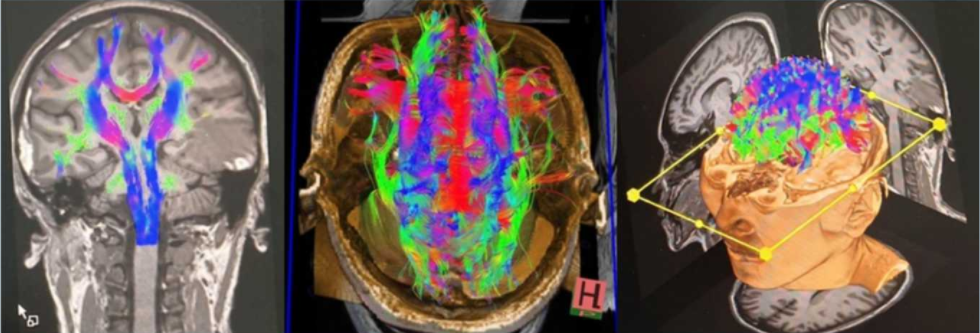

西门子3.0T磁共振不仅能“看”到神经系统的形态结构,更能“看”懂其功能状态。它支持多种先进的功能成像序列,如弥散张量成像(DTI)和功能磁共振成像(fMRI),这使其被广泛认为是神经科学研究和临床诊断的“金标准”。

脑肿瘤的“定位仪”:3.0T磁共振的高分辨率能够清晰显示肿瘤的大小、位置、边界及其与周围重要结构(如神经、血管)的关系。结合增强扫描和波谱分析等技术,还能帮助医生判断肿瘤的良恶性,为制定精准的手术方案或放化疗计划提供关键信息。